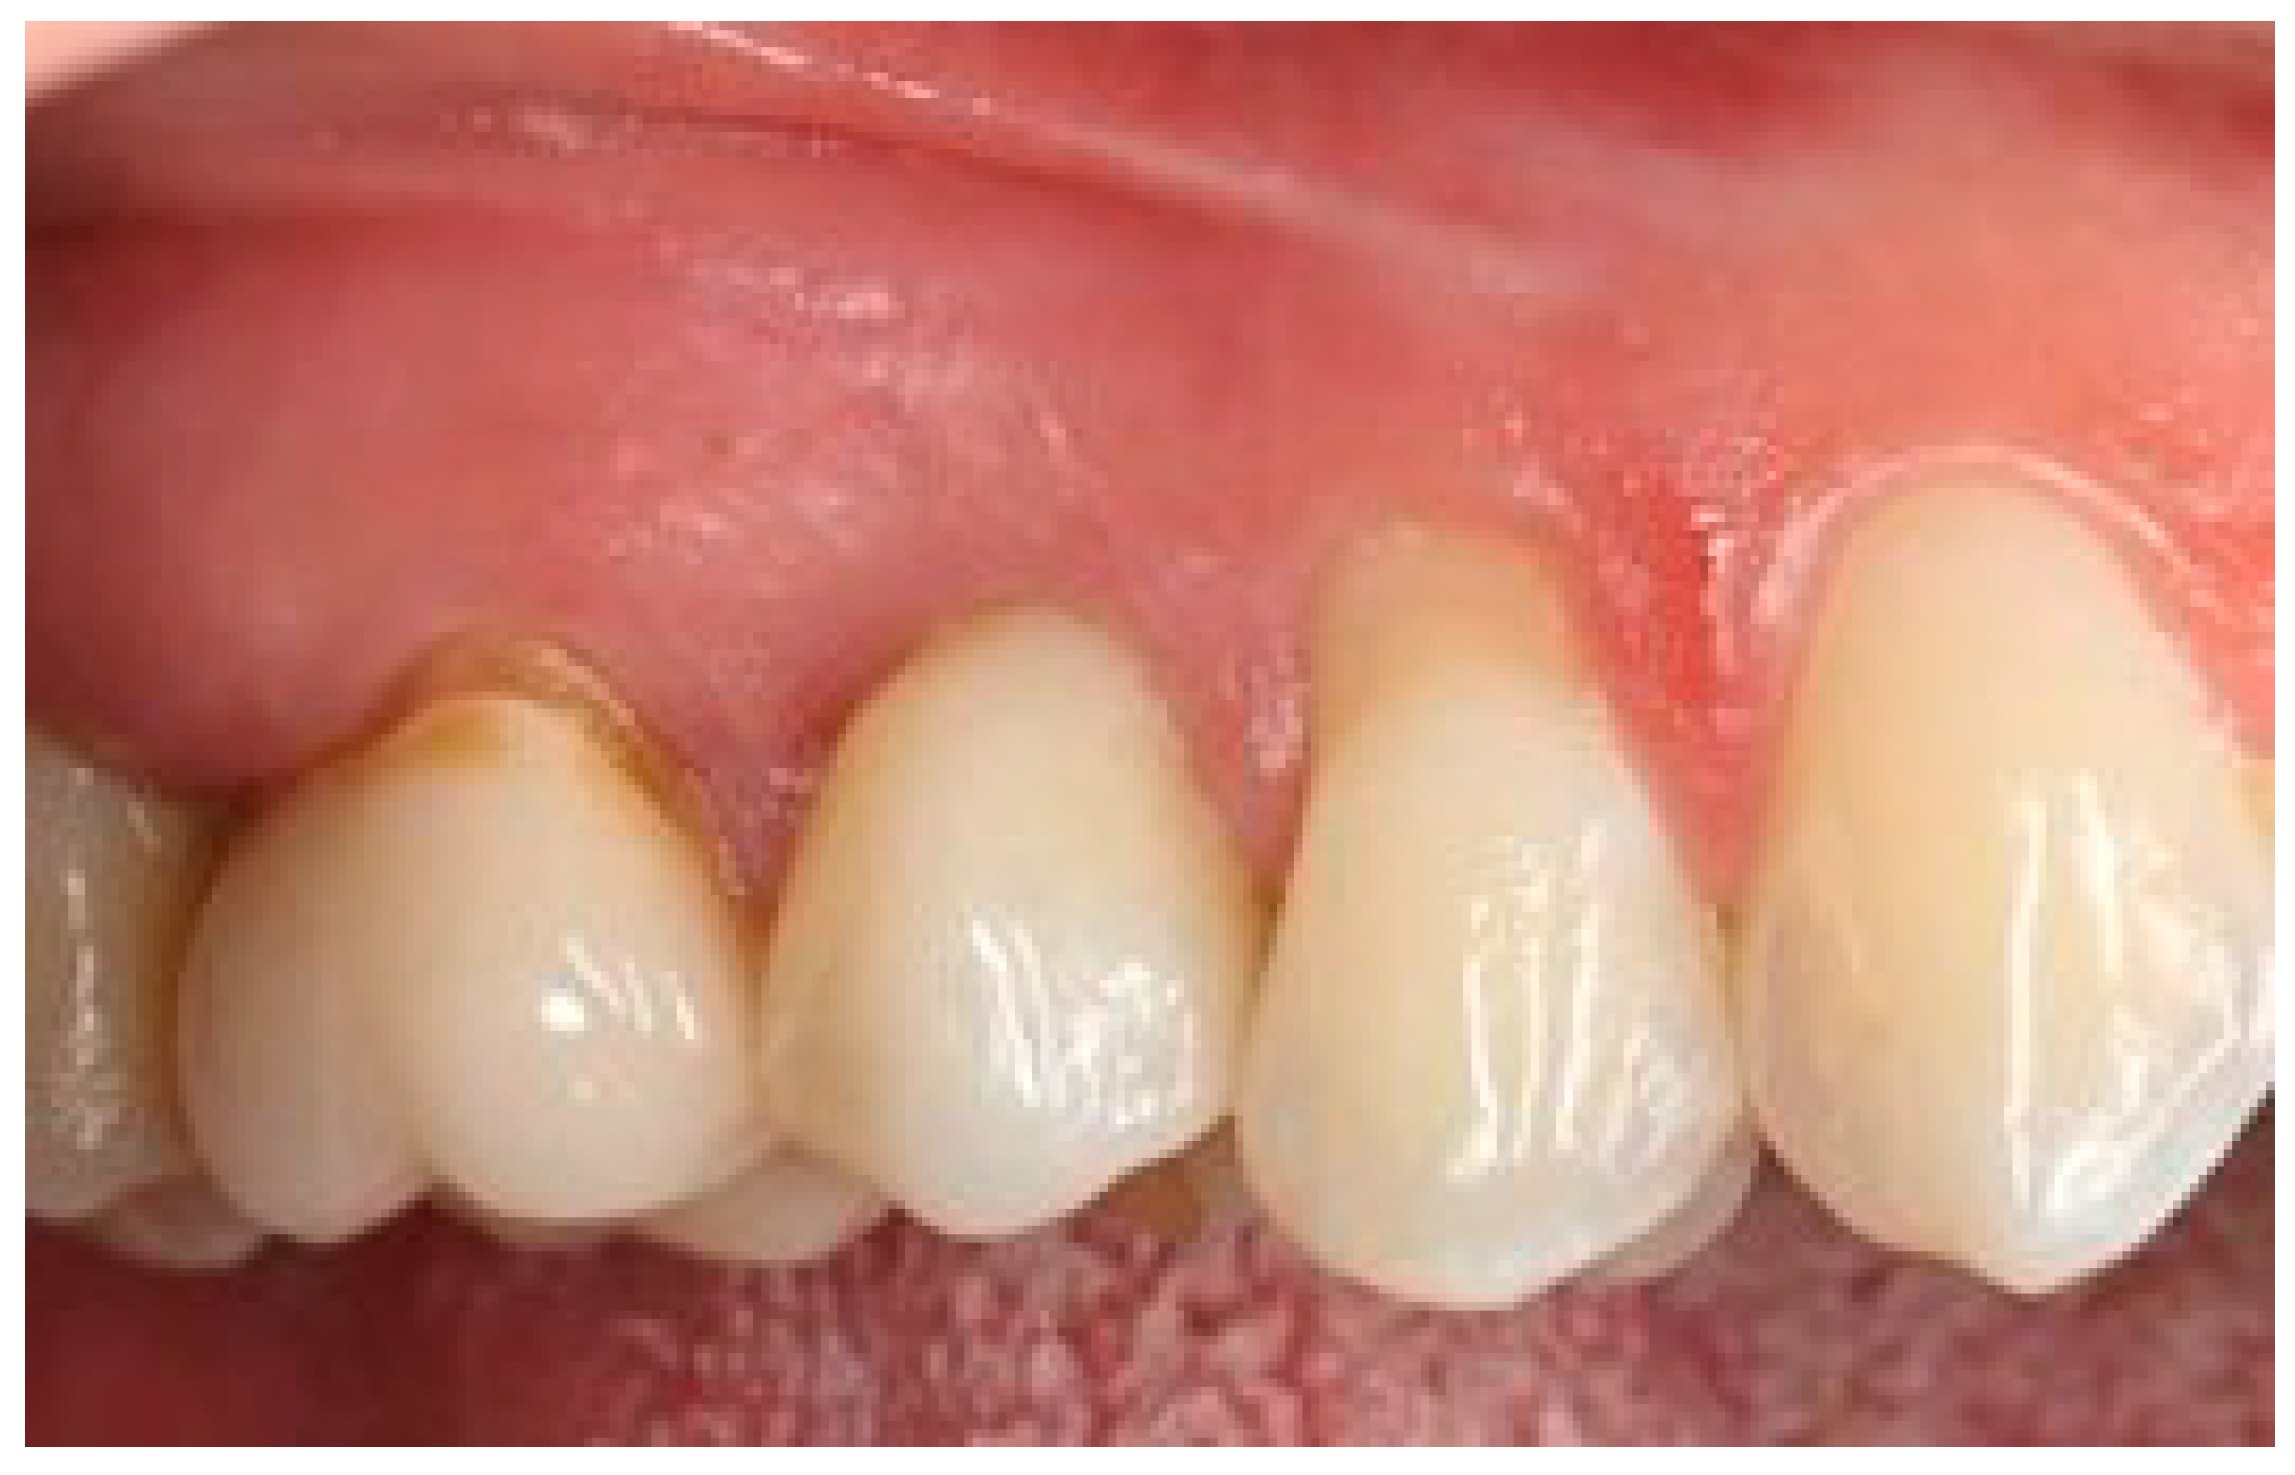

Figure 14 visualizes the mean distance between the soft tissue margin and fixture surface over time, from three months (T1) to 5 years (T3), for both the test and control groups. The error bars represent the standard deviation for each mean value, providing a visual representation of the variability within each group at each time point. At baseline and 3 months, there were no significant differences between the test and control groups (p > 0.05). At 1 year and 5 years, the test group showed significantly smaller distances compared to the control group (p < 0.01 and p < 0.001, respectively). The test group demonstrated a gradual decrease in distance over time, while the control group showed a slight increase. The clinical aspects are shown in Figure 15 and Figure 16.

Figure 16.

Five-year follow-up. Element 1.5 of the same patient.